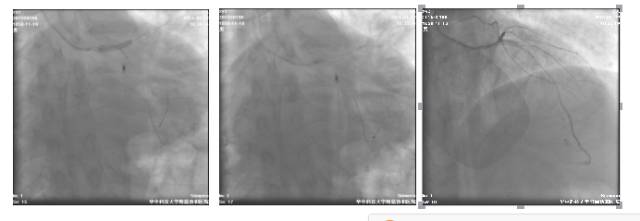

冠脉造影检查+急诊PCI

◆16:15 右冠状动脉造影:右冠近端轻度狭窄,第二屈膝部中段狭窄约50%

◆16:16 蜘蛛位造影示左主干中段以远急性闭塞

◆16:20 BMW导丝通过病变到达前降支远端

◆16:22 2.0×20mm Tazuna球囊扩张后退回左主干,显示左主干体部至末端高度狭窄并血栓

◆16:34 球囊扩张后于左主干起始部-前降支近端植入4.0×18mm Partner支架一枚,并与回旋支近端行对吻

◆16:35 PCI术后(肝位)

◆16:36 PCI术后(头位)